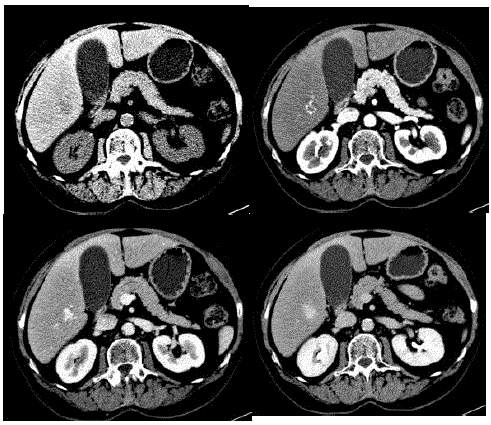

Mulher de 33 anos, em uso de anticoncepcional oral há 18 anos, realiza tomografia em investigação de dor abdominal, que evidenciou o nódulo hepático mostrado na imagem a seguir:

Qual é a melhor conduta?